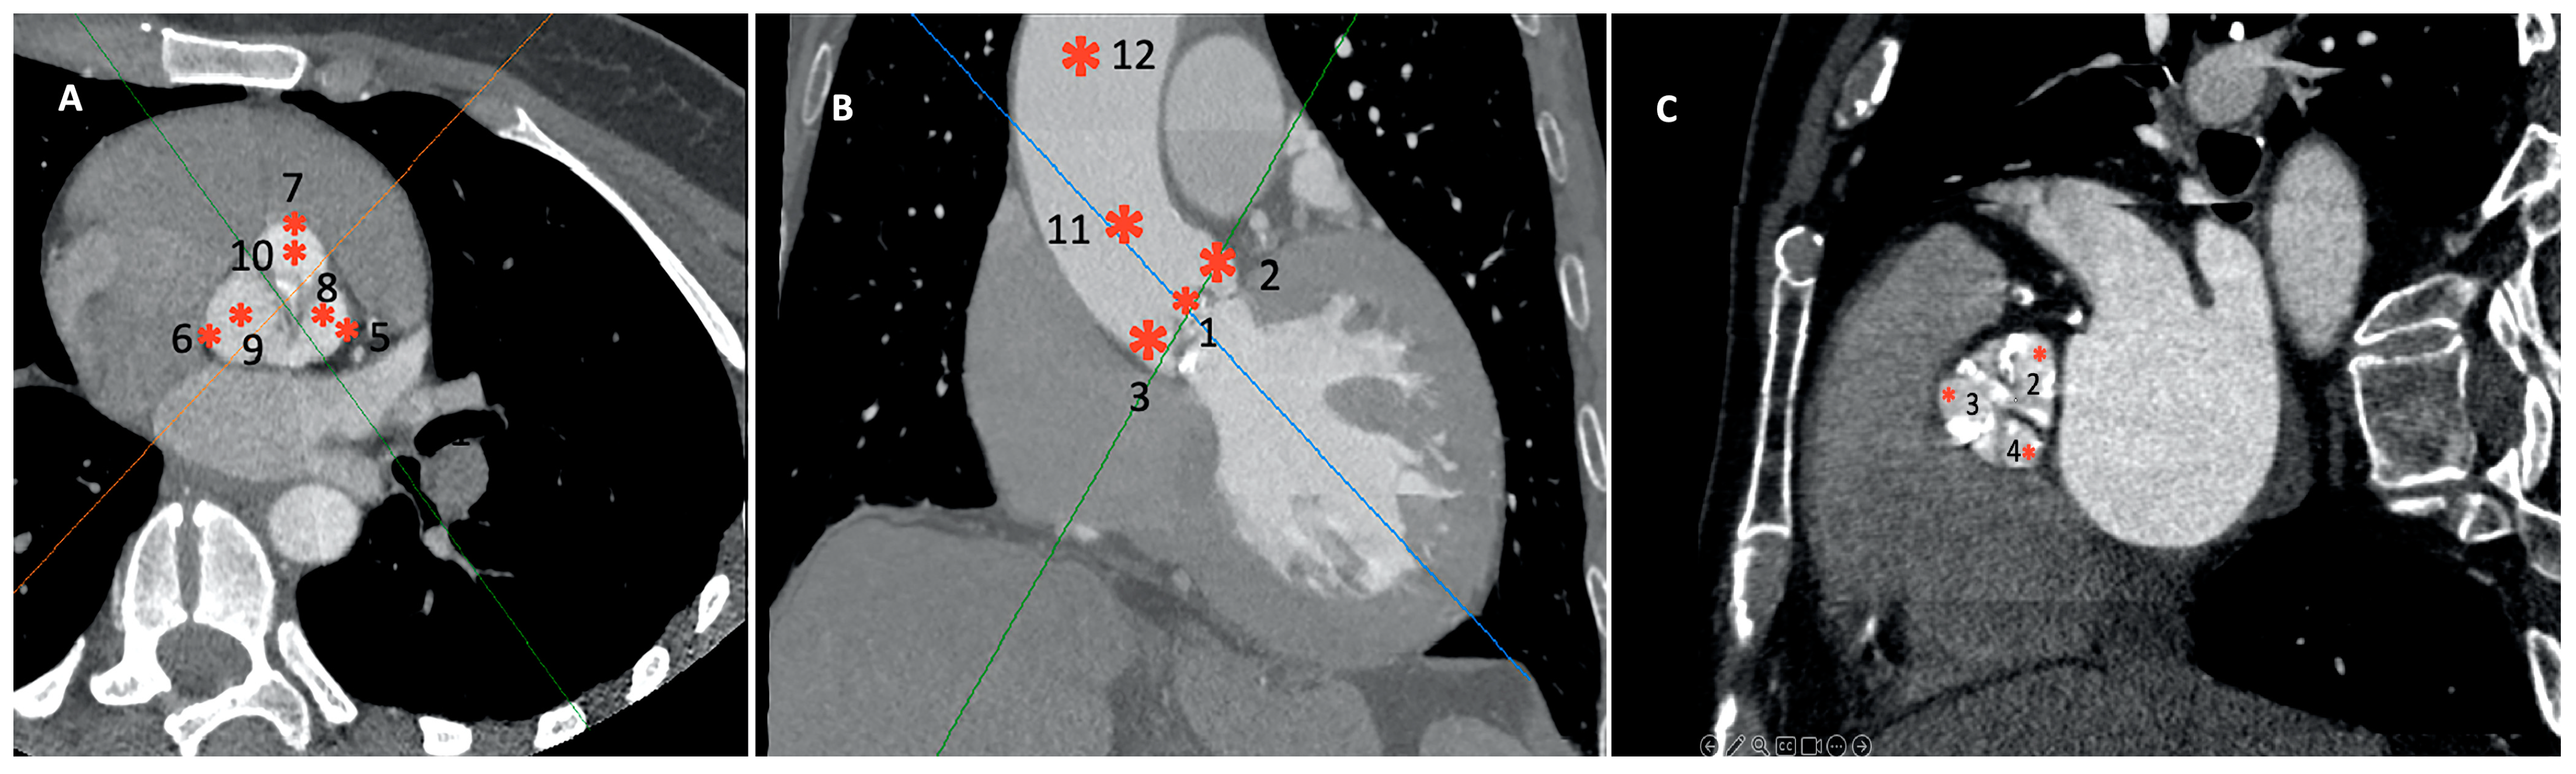

- Twelve distinct regions in 3D reconstruction mode: 4–5 mm above the opening of the aortic valve (OAV); at the junction of the leaflets and the fibrotic annulus (left, AL; right, AR; and non-coronary, AN); the mid-level of the sinus of Valsalva at the most lateral (Valsalva lateral left, VLL; Valsalva lateral right, VLR; and Valsalva lateral non-coronary, VLN) and at the mid-point (Valsalva center left, VCL; Valsalva center right, VCR; and Valsalva center non-coronary, VCN); and in the midline of the sinotubular junction (STJ) and 4 cm from the SJT (Figure 2). The region of interest was 3–5 mm2. Patients with a high grade of the beam-hardening effect due to severe calcification limiting the evaluation were excluded.